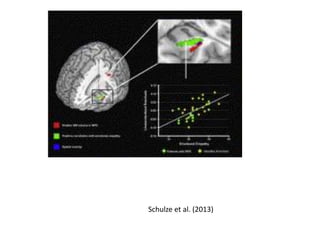

Schulze et al. (2013)

• #15 Left: In healthy participants, brain imaging scans show activity in the bilateral anterior insula in response to the amount of offers in an investment-style game. The graph shows an inverse relationship between insula activity and investment amount—high levels of activity in response to low offers, perceived by this brain region as unfair; decreasing response as the investment offer increases. Right: In participants with borderline personality disorder, activity in the bilateral anterior insula does not have a direct relationship with investment amounts.